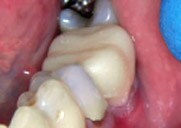

Figure 1

Initial situation:

Decay, fractured buccal cusp and unsupported lingual cusp on tooth

No. 20, buccal view.